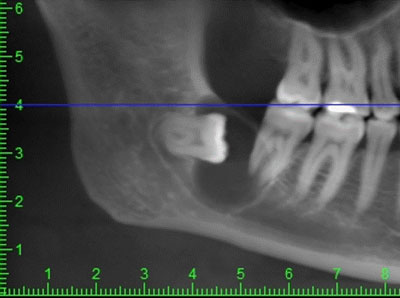

Перед удалением «восьмерки» врач сделает рентгеновский снимок (или КЛКТ, что будет лучше). Если ситуация сложная, вам разъяснят риски, так вы будете «морально готовы» к возможным осложнениям.

Непрорезанные восьмые зубы (зачатки) могут спровоцировать всевозможные воспаления десны, вызвать кариес, доставить болезненные ощущения. Конечно, не все зубы мудрости, оставшиеся непрорезанными, несут опасность, но в любом случае, сразу удалять их не стоит, за ними нужно наблюдать.Человек, у которого не появились зубы мудрости (один, два, три или все четыре), часто самостоятельно не может понять, есть ли они у него, либо ему повезло - и их нет даже в зачатках. Чтобы это определить, нужно пройти рентгенологическое обследование, как минимум, сделать обзорный панорамный снимок (ОПТГ), либо пройти современную конусно-лучевую компьютерную томографию (КЛКТ). Все эти обследования вы можете пройти в нашей клинике.